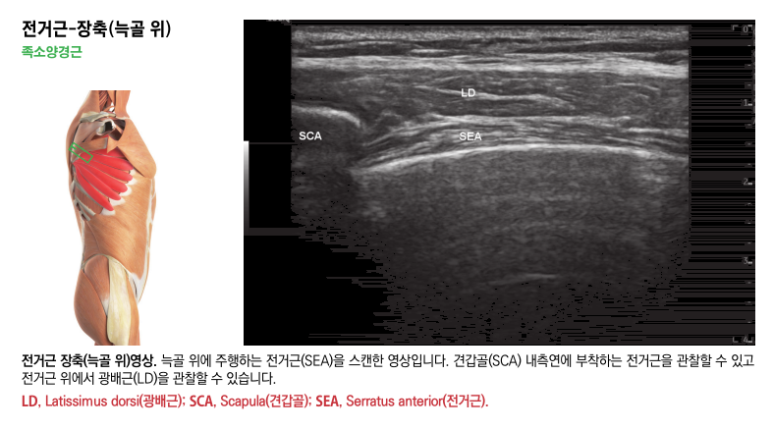

@ 초음파로 보는 알짜 근육학 위 영상은 제가 출판한 초음파 전공서적인데요. 문제가 있는 ## 족소양경근의 혈자리*를

초음파 영상으로 살펴보면

깊이에 따라

광배근, 전거근과

견갑골, 늑골이 보입니다.